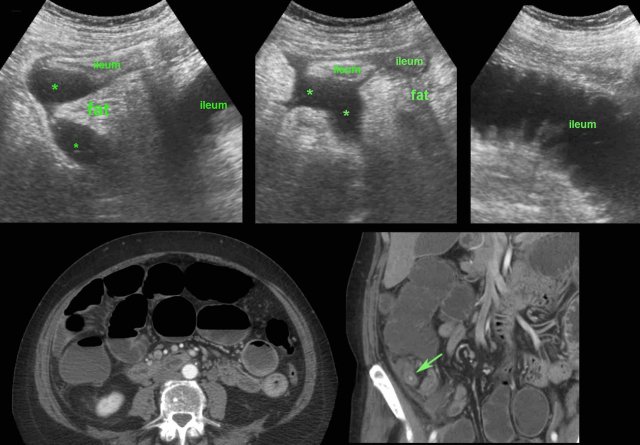

US showed a combination of thickened ileal loops, paralytic ileus, inflamed fat and ill-defined fluidcollections (*), but no inflamed appendix or other cause of bowel perforation.

CT confirmed paralytic ileus and an inflamed appendix (arrow).

Surgery revealed severely contaminated purulent peritonitis from perforated appendicitis.

US and CT often show a large mass of non-compressible fat around the appendix, often also with wall thickening of neighboring bowel loops.

If there is a circumscribed pus collection, the diagnosis is appendiceal abscess. If not, the diagnosis is appendiceal phlegmon.

Patient with a small appendiceal abscess, ventrally walled-off by the ileum.

The appendix (arrows) is small because it has evacuated its purulent contents in to the abscess.

Note the calcified fecolith (arrowhead) on the bottom of the abscess.

Drainage was performed from laterally.